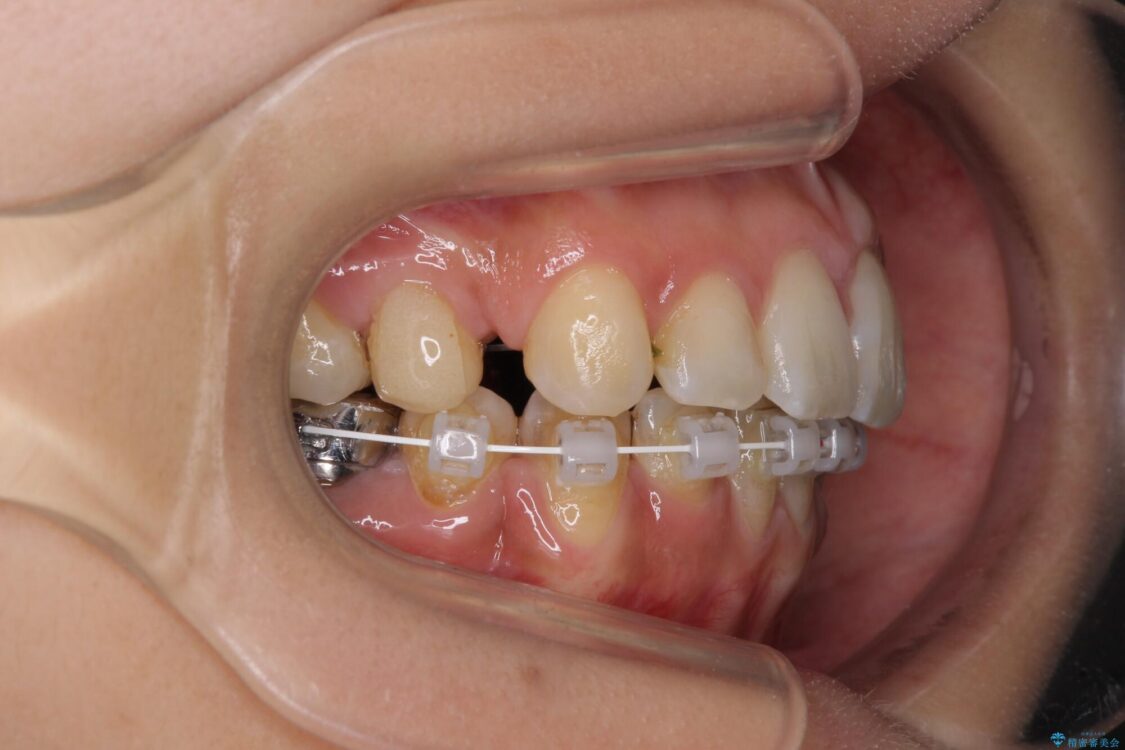

前歯のデコボコと上顎の前突感による口の閉じにくさを気にして来院された患者様です。

目立たない装置を希望されたので、上顎が裏側装置のハーフリンガルを選択し、上下左右の小臼歯(計4歯)を抜歯して矯正治療を行うこととしました。

治療途中

• デコボコと口元の突出感 ハーフリンガルでの抜歯矯正 治療途中画像